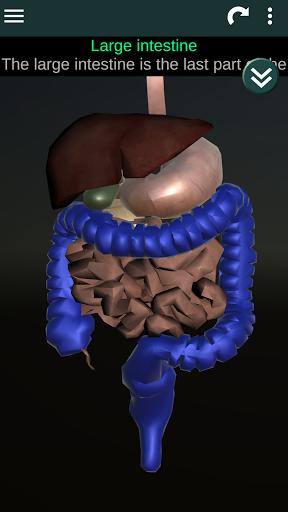

(الأجهزة الداخلية في)

Internal Organs 3D Anatomy 3.4

يمكنك هنا تنزيل ملف حزمة تطبيق أندرويد "Internal Organs 3D Anatomy" الخاصة بجهازVodafone Smart N9 Lite مجانًا، نسخة ملف حزمة تطبيق أندرويد - 3.4 للتحميل على Vodafone Smart N9 Lite اضغط ببساطة على هذا الزر. إنه سهل وآمن. نحن نقدم فقط ملفات حزمة تطبيق أندرويد الأصلية. إذا انتهكت أية مواد موجودة في الموقع حقوقك قم بإبلاغنا من خلال